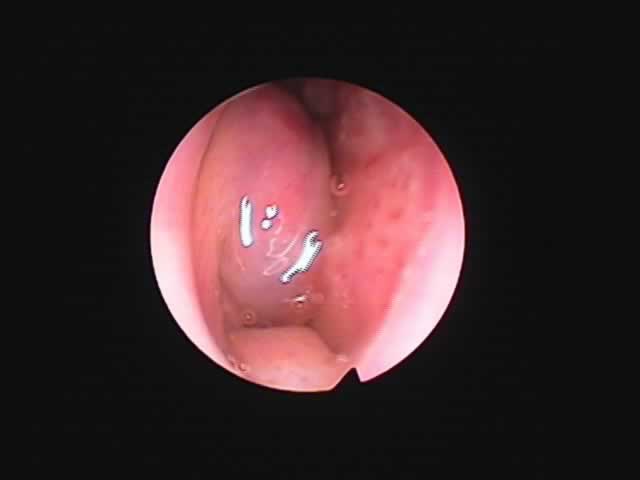

| 7月16日 かなり縮小 | 両手術直後(縮小不十分なため追加焼灼、8月9日) | 9月8日 著明に縮小しいびき消失しているとのことです |